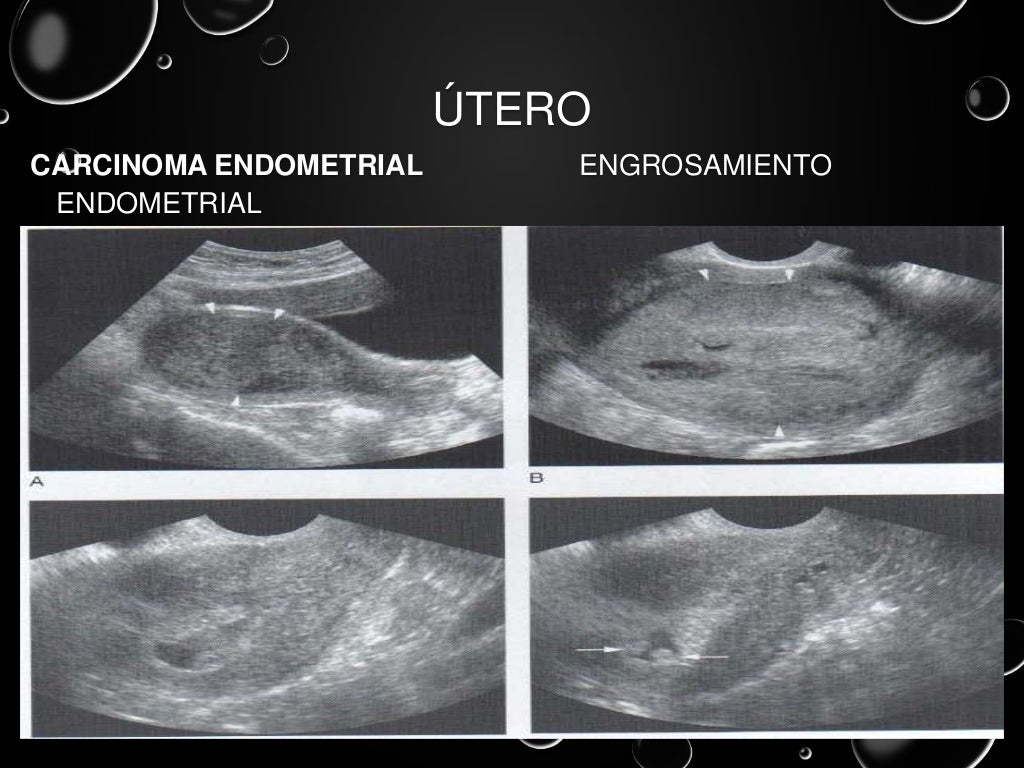

ULTRASONIDO TRANSVAGINAL PARA LA DETECCIÓN PREOPERATORIA DE

Source: sochog.cl